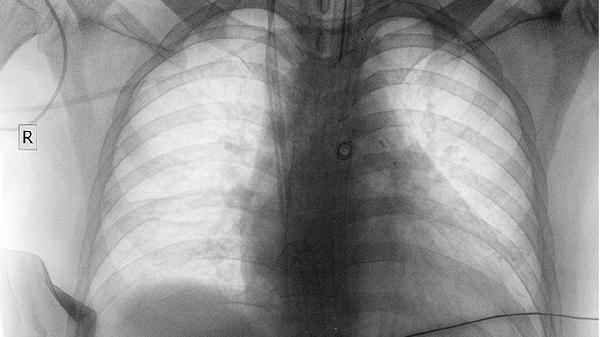

肺癌复发可能出现咳嗽加重、痰中带血、胸痛、呼吸困难、体重下降等症状。肺癌复发通常由肿瘤残留、治疗不彻底、免疫力低下等因素引起,表现为原有症状再现或新发症状。建议患者定期复查,出现异常及时就医。